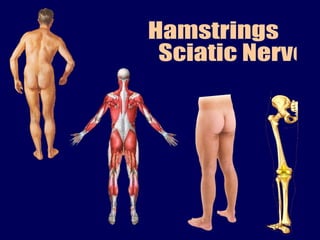

Hamstrings sciatic nerve

This document provides information about the sciatic nerve and muscles it innervates. It originates from the ischial tuberosity and inserts into the tibia and fibula bones of the leg. It is supplied by the tibial division of the sciatic nerve. The muscles it innervates allow for flexion of the knee and extension of the hip. These muscles include the semitendinosus, semimembranosus, and biceps femoris. Compression of the sciatic nerve can occur against the femur or from conditions like lumbar disc prolapse and can result in shooting pain along the nerve's cutaneous distribution.

- 6. Origin – Ischial Tuberosity Insertion – Bones of leg Tibia / Fibula Supplied by Tibial division of Sciatic Nv. Flexors of knee and extensors of Hip Semitendinosus Semimenranosus Biceps Femoris Ischial part of Adductor Magnus

- 14. Biceps Femoris iLio tibial tract Rt. Knee lat. Side

- 17. SACRAL PLEXUS – SCIATIC NERVE Dorsal divisions Ventral divisions L4 L5 S1 S2 S3 Lumbosacral trunk Superior gluteal Inferior gluteal Sciatic nerve Common peroneal part Tibial part Q.Femoris / Inf.Gem. Obt.Int. Post.cut.nr.of thigh. Piriformis

- 22. Compression of nerve against femur - Unusual stretching after sitting for long time “ Sleeping foot” - Shooting pain along cutaneous distribution of sciatic nerve – begins in gluteal region; radiates to back of thigh, lateral side of leg, dorsum of foot. - Compression of sciatic nerve by Osteoarhtitis, Lumbar disc prolapse, spondylolisthiasis, Fibrositis, Neuritis etc. penetrating wounds, dislocation / fracture of pelvis – foot drop and sensory loss.

- 24. VERTICAL LINE HORIZONTAL LINE HIGHEST P[OINT OF ILIAC CREST SAFE INJECTION REGION SCIATIC NERVE ISCHIAL TUBEROSITY